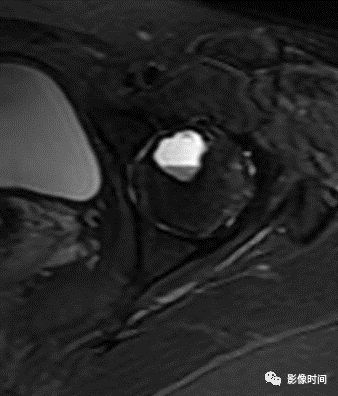

九、瘤周水肿

肿瘤周边的骨髓水肿表现为 T1WT 低信号和 T2WI、STIR 高信号边界模糊的片状影,软组织肿块邻近的正常软组织成分,尤其是肌肉内亦可出现水肿,表现为肿块周围沿肌束方向分布的边界模糊的片状或羽毛状影,有时可连成片。瘤周水肿常见于恶性肿瘤(图 58),但也可见于某些良性肿瘤如软骨母细胞瘤(图 59)、骨样骨瘤和骨嗜酸性肉芽肿(图 60)等。

图 58   瘤周水肿:骨肉瘤

图 59 瘤周水肿:软骨母细胞瘤

图 60  瘤周水肿:骨嗜酸性肉芽肿